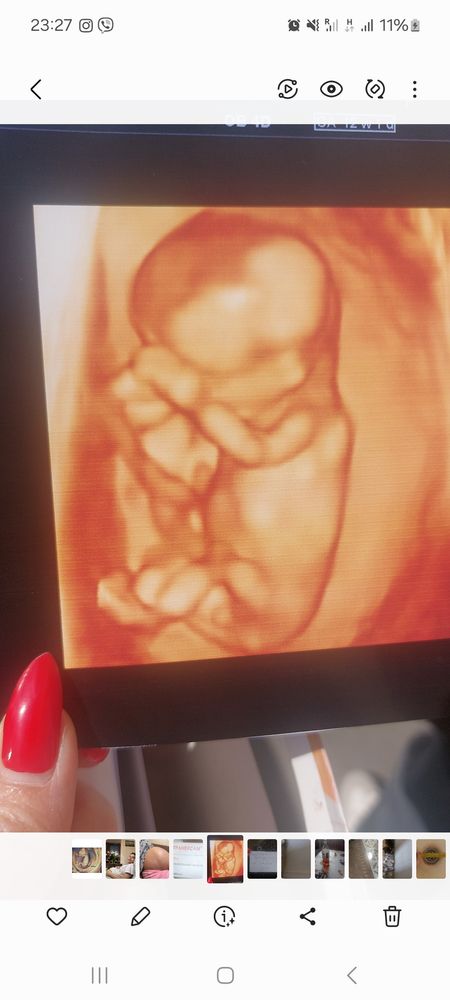

Узи 13 недель

Если на первом фото вот то, что торчит вверх - это половой бугорок, то мальчик:)

Я вижу девочку, но это не 100%, так как ракурс не очень удобный для меня

Ракурс не тот, не видно. Остаётся гадать🤗🌷🌷🌷

Людмила, на скриниге сказали мальчик☺️ но после моих девченок я в такое не верю😄

Anna Сагумян, ой, первое фото не увидела 🙏 там на девочку больше похоже, но врачу виднее. Пусть будет мальчик🤗Если бы мне сказали, что у меня девочка, я бы тоже не поверила😄

По этому фото сложно сказать. Но я предположу мальчика. Но это больше пальцем в небо